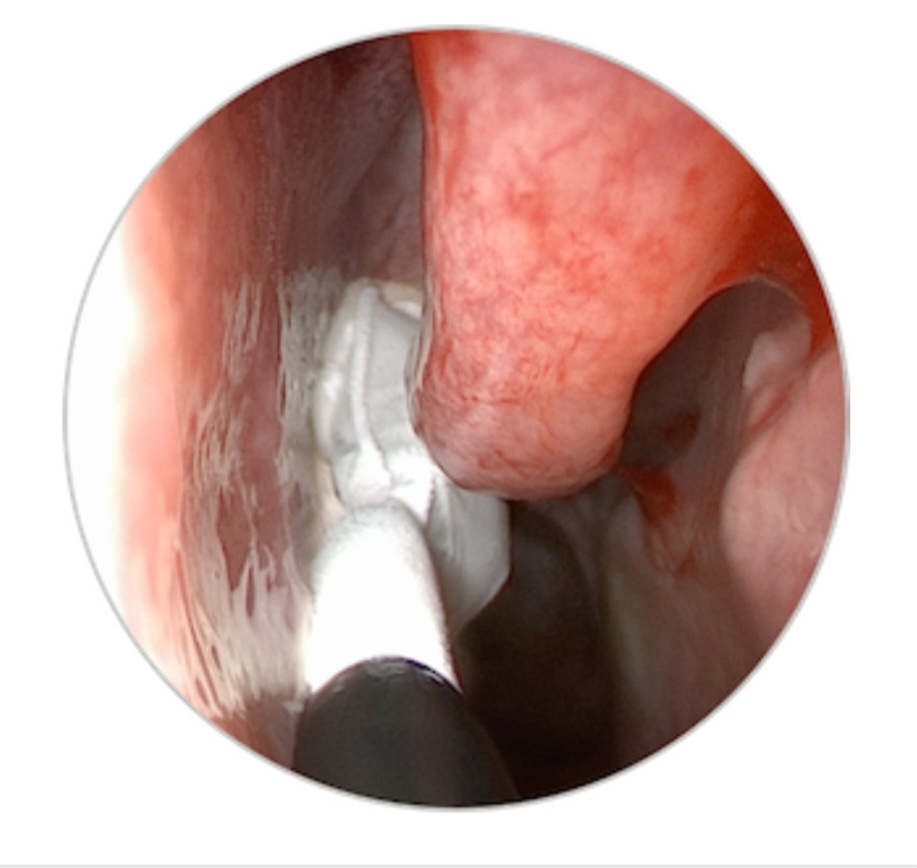

Cryotherapy sessions for chronic rhinitis typically involve the application of controlled cold temperatures to the nasal passages. These sessions are performed by trained healthcare professionals using specialized cryotherapy devices. The duration and frequency of treatment may vary depending on the severity of symptoms and individual patient response. Generally, a series of sessions over several weeks is recommended to achieve optimal results.

Cryotherapy is generally considered safe, with minimal adverse effects reported in clinical studies. Some patients may experience temporary discomfort, mild nasal bleeding, or a sensation of pressure during the procedure. It is essential to consult with a healthcare professional experienced in cryotherapy to ensure appropriate administration and to address any concerns.